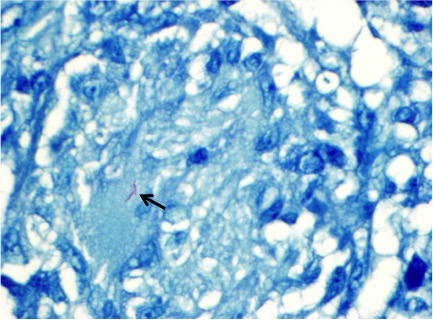

Case Presentation: A 22-year-old Hispanic male presented with a 4 day history of rectal and abdominal pain. He denied any previous medical history. He also noted three months of productive cough, pyrexia, chills, night sweats, fatigue, and weight loss. Physical examination revealed right lower quadrant tenderness accompanied by abdominal rigidity and involuntary guarding. The patient declined digital rectal examination. Labs were normal. Chest xray revealed biapical pleural thickening associated with parenchymal scarring, bronchiectasis, nodularity, and and superimposed infiltrates. CT of the abdomen revealed acute appendicitis and a peri-rectal abscess. The patient underwent laparoscopic appendectomy and drainage of the peri-rectal abscess. This was followed by bronchoscopy with BAL. Sputum, BAL, and cultures from peri-rectal abscess were positive for acid-fast bacilli. Histologic examination of the appendix revealed granulomatous inflammation with central necrosis, multi-nucleated giant cells, and acid-fast positive bacilli confirming tuberculous enteritis.

Discussion: Mycobacterium Tuberculosis (TB) is the second most common infectious cause of death worldwide. It may manifest in any organ system and mimic many different diseases. The respiratory system is most commonly affected. When the gastrointestinal system is involved, it is referred to as tuberculous enteritis. The ileocecum is most often affected with appendicular involvement a rare occurence. There are four main mechanisms which may lead to tuberculous enteritis. These include swallowing of infected sputum in active pulmonary tuberculosis, ingestion of contagious milk from cattle infected with bovine TB, direct extension from adjacent organs, and hematogenous spread. Once the bacillus enters the gastrointestinal, tract it traverses the mucosa to lodge in the submucosa leading to inflammatory changes including cellular infiltration, lymphatic hyperplasia, serosal, and submucosal edema. The eventual result of inflammation is production of granuloma which causes small papillary mucosal elevations, lymphangitis, endarteritis, and fibrosis. In due course mucosal ulceration develops along with caseating necrosis, and narrowing of the intestinal lumen leading to obstruction. We believe this patient may have either ingested sputum from active TB or he developed hematogenous spread from the pulmonary focus. Fortunately he presented earlier on in the disease process. He was started on Rifampin, Ethambutol, Isoniazid, and Pyrazinimide and achieved convalescence with further surveillance tests at different time intervals returning negative.